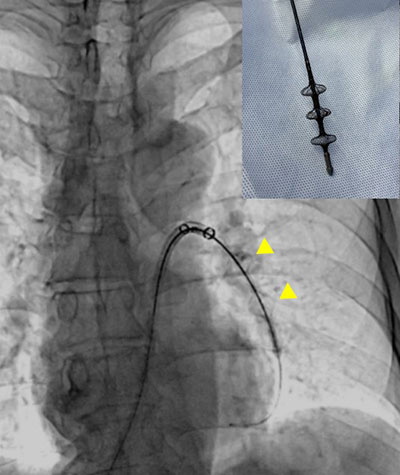

Tendvia取栓

取出的血栓

为了预防再次肺栓塞的发生,科室同期行下腔静脉滤器植入术及左下肢Angiojet血栓清除术。应用肺动脉取栓的同一入路,右侧股静脉放置滤器后,翻山至左下肢静脉,造影明确左下肢混合性血栓,由肌间静脉延伸至髂静脉,经Angiojet吸栓后左下肢深静脉完全复通。